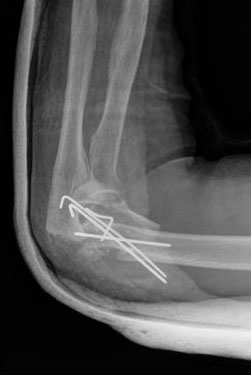

Fractura supracondílea de codo. Tratamiento con agujas.